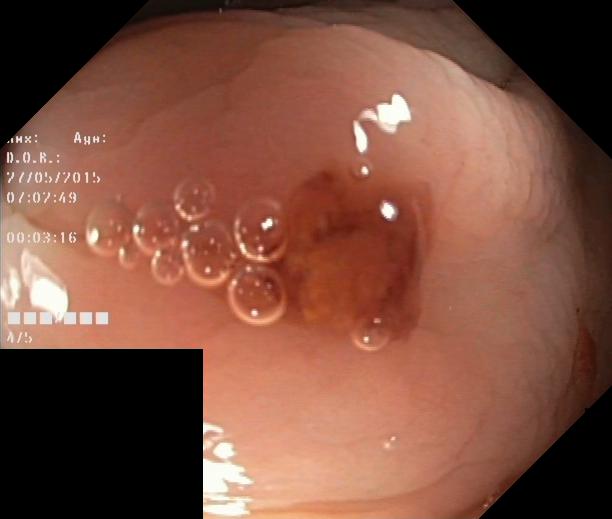

As part of the EndoCV2021 challenge (https://endocv2021.grand-challenge.org/), we were tasked with creating machine learning models that automatically segment polyps [11, 12, 13] in video frames collected from real-world endoscopies. This is a complex task as polyps come in various shapes and sizes, where some (e.g., flat lesions) are barely detectable by even the most experienced endoscopists. Figure 1 shows some of the more difficult examples taken from EndoCV’s development dataset [10] provided by the challenge organizers. The challenge presented two separate tasks, the detection generalization challenge and the segmentation generalization challenge. We participated in the segmentation generalization challenge, where we achieved the best results among 13 other competitors in both rounds. The code for the experiments presented in this paper is available on GitHub111https://github.com/vlbthambawita/divergent-nets.

Figure 4 shows some example masks predicted by our best performing model (DivergentNets) together with masks produced by the intermediate models. We see that each intermediate model learns slightly different features, making an overall more precise segmentation mask when combined. For example, the first row of Figure 4 shows the predicted masks and ground truth of a large polyp. We see that each model predicts slightly different masks for the same input and that TriUNet over-estimates the size of the polyp. After averaging the predicted masks for DivergentNets’ final output, this area is smoothed out by the predictions from the other intermediate models.

Even though DivergentNets primarily produces more accurate masks than any single model, there are cases where masks from the intermediate model better match the ground truth. We see this in row three, where DeepLabv3+ produces a more precise mask than all other intermediate models, making the averaged output less accurate.